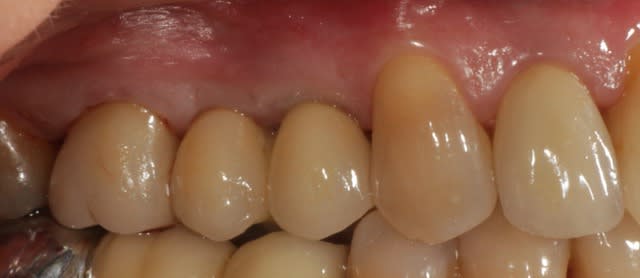

et la fin.

Superbe résultat !

Par contre si je peux me permettre, tu devrais y aller mollo sur les filtres pour tes radios, sur le cliché présenté l'os paraît un peu bizarre, on pourrait presque croire que les implants ne sont pas ostéointégrés.

C'est beau, j'en ai la larme à l'oeil...

J'espère que ton patient est satisfait (le contraire serait écœurant). Ce résultat ne peut que durer, vu la qualité de ton travail et la qualité de ces implants.

Félicitations.